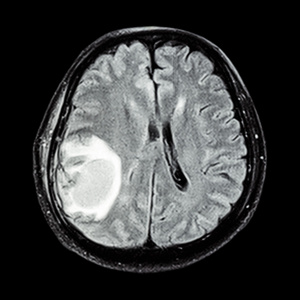

磁共振脑在右顶叶脑肿瘤

右侧额顶叶占位脑膜瘤可能